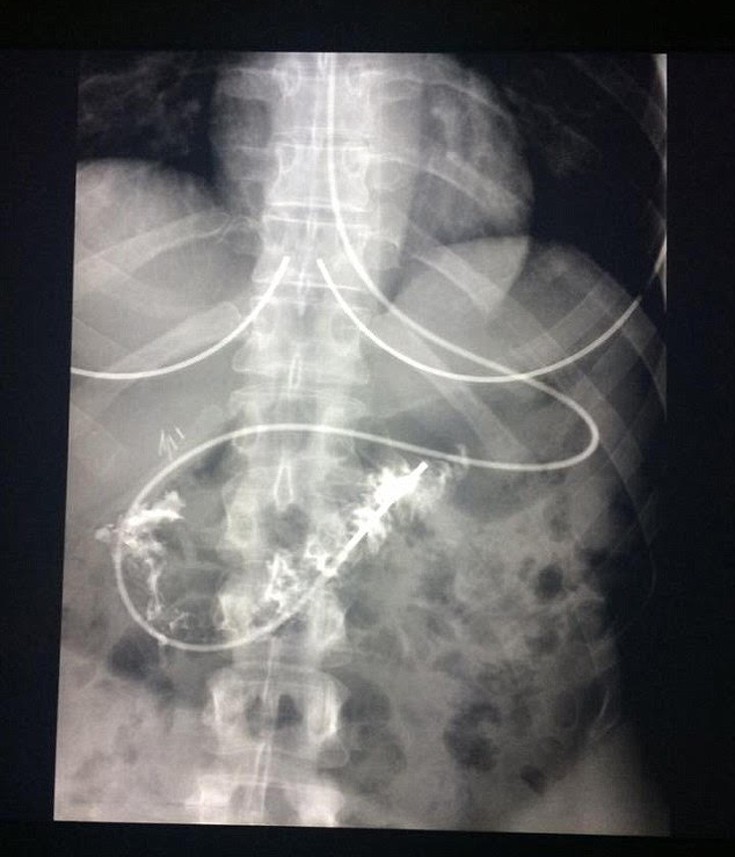

H Charmain Walker-Caunt από την Αυστραλία είναι μια νεαρή γυναίκα που έχει παραιτηθεί πλέον από το να ζει μια κανονική ζωή εξαιτίας του προβλήματος υγείας που έχει. Όπως αναφέρει η ίδια, το πεπτικό της σύστημα είναι παράλυτο και ο «σύντροφος της ζωής της» είναι ένας σωλήνας δύο μέτρων που τροφοδοτεί τον οργανισμό της με θρεπτικά συστατικά μέσα από το αριστερό ρουθούνι της. Αυτό που ελπίζει, πλέον, η 35χρονη είναι να μπορεί τουλάχιστον να ελέγχει τη σταθερή ναυτία και τον εμετό και τότε ίσως η «μισή κανονική ζωή» θα μπορούσε να είναι εφικτή.

Η γυναίκα πάσχει από μια σπάνια ασθένεια που ονομάζεται γαστροπάρεση. Έχει κυριολεκτικά παραλύσει το πεπτικό της σύστημα από το λαιμό της ως τα σπλάχνα της. Πιο απλά αυτό σημαίνει, όπως αναφέρει η Daily Mail, ότι ένα τρόφιμο δεν χωνεύεται στο στομάχι της και ακόμη και αν φάει ένα κομμάτι τοστ, αυτό θα της προκαλέσει εμετό για έξι ή επτά ημέρες μέχρι το σώμα της να απορρίψει και το τελευταίο ψίχουλο.

«Έχω πλήρως παραλύσει από τον οισοφάγο και από το στομάχι στο μικρό έντερο» λέει η ίδια περιγράφοντας την κατάστασή της ενώ όπως λέει χαρακτηριστικά είναι σαν να πεθαίνει από την πείνα και να έχει μπροστά της ένα μπέργκερ το οποίο δεν μπορεί να φάει. Κάθε φορά που μπορεί να δοκιμάσει να φάει κάτι, το στομάχι της συγκλονίζεται και κάνει μέρες για να το ξεπεράσει. Η ίδια περνά το μεγαλύτερο μέρος της ζωής της φοβούμενη για σποραδικές εξάρσεις εμετού που έρχονται χωρίς προειδοποίηση. Τροφοδοτείται μόνο από το σωληνάκι και προσπαθεί να συνηθίσει αυτό τον τρόπο ζωής δίνοντας τον δικό της αγώνα.